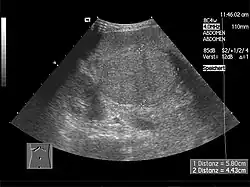

Elle est peu spécifique et sert essentiellement à détecter certaines causes rares ou des complications (cancer du foie).

L'échographie abdominale montre un parenchyme hépatique hétérogène et nodulaire, contours bosselés, avec une hypertrophie du segment I ou lobe caudé, des signes d'hypertension portale avec augmentation de la taille de la rate (splénomégalie)…

Le scanner et l'IRM sont meilleurs que l'échographie pour détecter un cancer du foie[2]. L'IRM est également fiable pour détecter certaines causes, notamment l'hémochromatose, par la mesure de la concentration en fer des tissus[15]. La fibroscopie œsogastrique peut retrouver des varices œsophagiennes, signe d'hypertension portale.